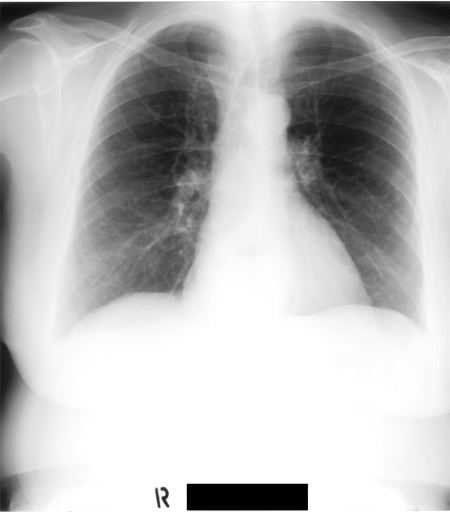

Figure 2 shows barcode annotations for two medical images from IRMA dataset [34, 35] for different values (see lines 4 and 10 in Algorithm 1). Hence, the algorithm works with equidistant angles of projection.

Radon barcodes are binarized versions of Radon projections. To create the optimal Radon barcodes (barcodes that are highly expressive to tag digital images in a unique way such that they can be retrieved easily), one has to find the optimal projections. Since we are trying to find projections, we should find a fitness function that guides micro-DE in the right direction. If the projections are good (compared to all other possible combinations), then image reconstruction using these projections should yield smaller error compared to all other combinations. Figure 3 shows for the chest x-ray that the 4 best projections by examining all 1820 combinations when 16 equidistant projections are available.

In this section, we report two series of experiments. The first one verifies the correctness or reliability of the micro-DE algorithm to find optimal projections compared to an exhaustive search when we are looking for 4 optimal projection angles out of 16 equidistant angles. In the second experiments, we still provide the results for exhaustive 4/16 selection but examine the evolutionary approach to get 4/180 and 8/180 to investigate the reconstruction accuracy of the micro-DE via correlation of the input image and the reconstructed image using 4/16 (exhaustive), 4/180 (micro-DE) and 8/180 (micro-DE). To conduct the experiments we used 50 images from IRMA dataset [34, 35], a benchmarking collection of 14,400 x-rays images. We selected 10 random classes out of 58 classes, and for each class, we randomly drew 5 images to be used in our experiments. Figure 4 shows the images we have used.

In this series of experiments, we randomly selected three categories from IRMA dataset (namely, breast, foot and lung), and for each category we choose 5 random images from that class (Figures 5, 6 and 7 show these images). When we find “4 out of 180” (4/180) and “8 out of 180” (8/180) projections via micro-DE (tasks that cannot be performed via brute-force), then the question is what can we say about the reconstruction error, in terms of correlation between original and reconstructed images, when we compare evolutionary approximation with the case that we can manage via exhaustive search, namely “4 out of 16” (4/16)? Can micro-DE reach at least the same correlation (similarity) as the brute-force case in lower dimensions? If yes, we may have more confidence in using micro-DE in practice where we cannot apply brute force for benchmarking or direct use, especially for higher dimensions (i.e., the number of projections).